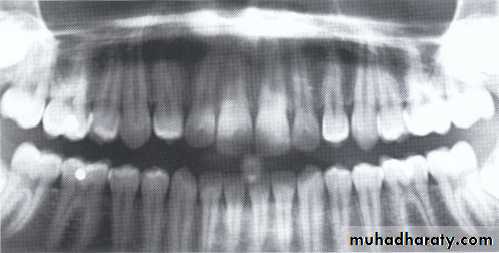

Developmental absence of all maxillary premolars and both mandibular second premolars. Note the retention of the maxillary primary canine as a result of the posterior position of the maxillary permanent canine.